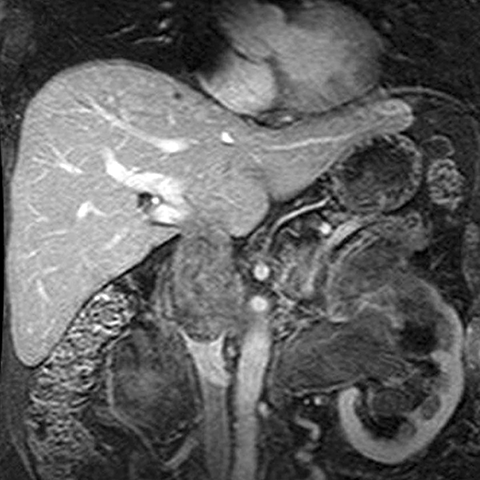

67-year-old male with flank mass and hematuria [3 of 3]